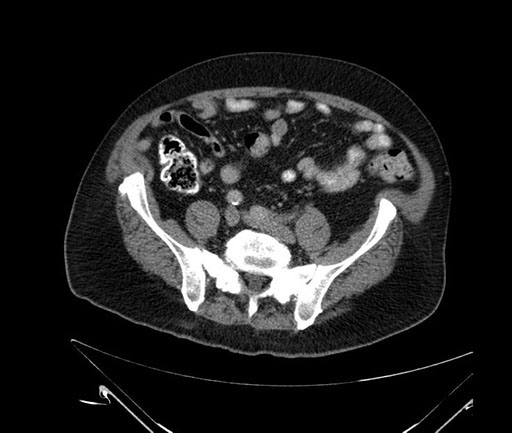

Imaging Analysis

Look through the patient's CT scan to identify any areas of concern for the necessary procedure.

Based on your CT findings, which issue(s) would give reason for "planned slowing down moment(s)" in this case?